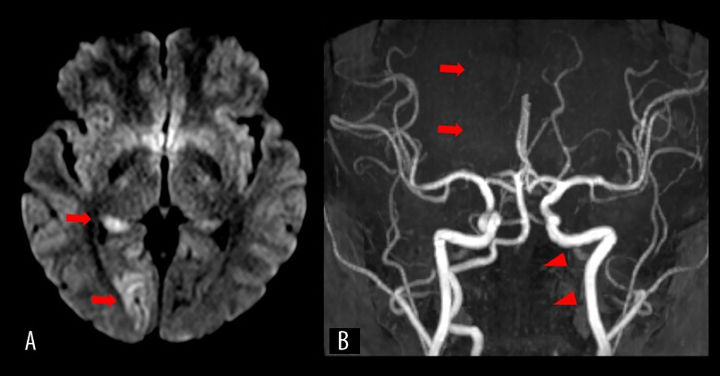

진단 결과 A씨는 격렬한 동작으로 인해 왼쪽 척추동맥 내막이 찢어지고, 이에 따라 혈액이 스며들어 혈전이 형성됐다. 이 혈전은 뇌 시각 중추로 가는 주요 혈관을 막아 허혈성 뇌졸중을 유발했다. 결과적으로 A씨는 양쪽 눈의 왼쪽 반쪽 시야를 잃고 왼쪽 반신 감각을 잃는 심각한 상태에 이르렀다.

A씨는 곧바로 혈전 제거술과 동맥 내 혈전용해술 받았으며, 이후 이중항혈소판제 치료가 이어졌다. 치료 이후 하루 만에 증상은 크게 호전됐고, 14일 만에 퇴원할 수 있었다. 퇴원할 때는 가벼운 시야 결손만 남았다. 추적 검사에서도 혈관이 회복되는 양상이 드러났다.